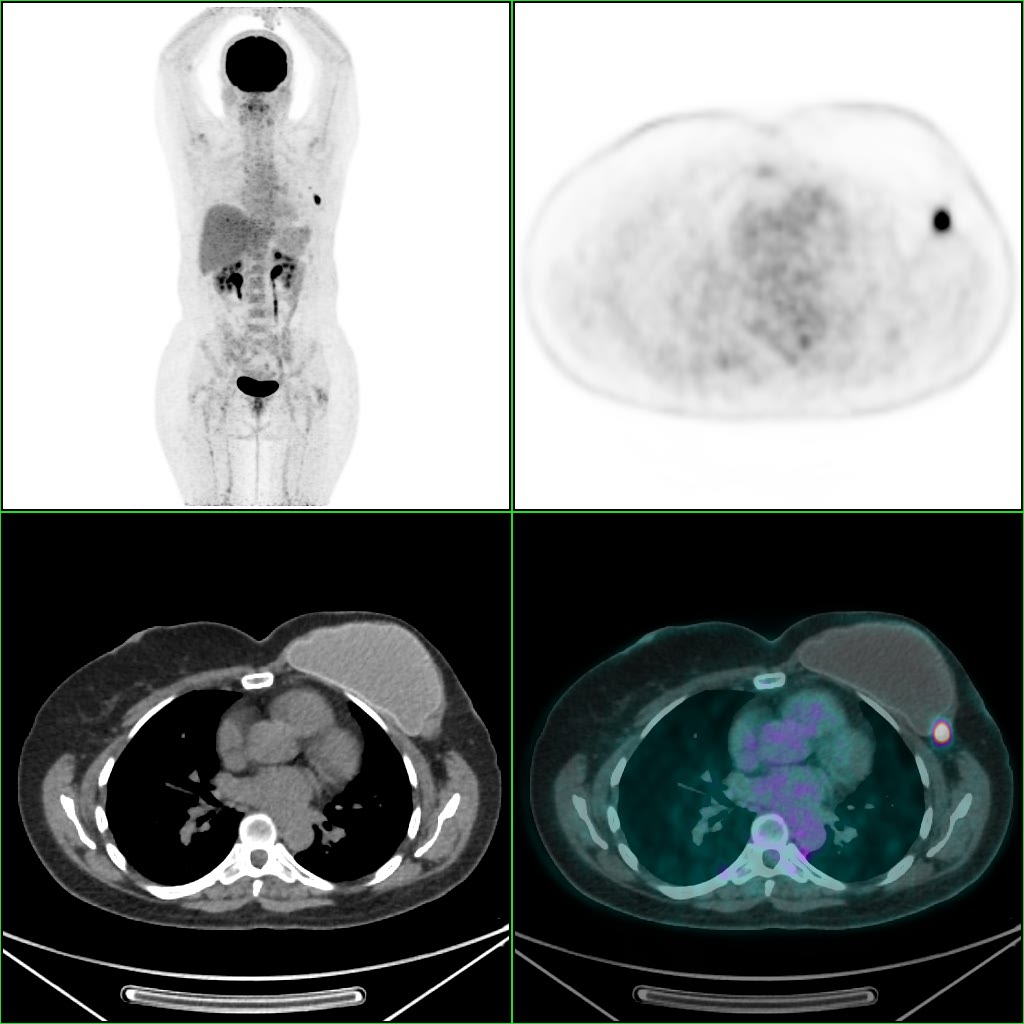

Figura 1 – PET/CT em paciente com neoplasia de mama e um linfonodo hipermetabólico. À esquerda, observa-se a imagem metabólica PET de corpo inteiro em 3D. À direita o linfonodo axilar demonstrado no plano axial, como as imagens são adquiridas no estudo tomográfico e na imagem metabólica, sendo realizada após a fusão das informações em PET/CT.